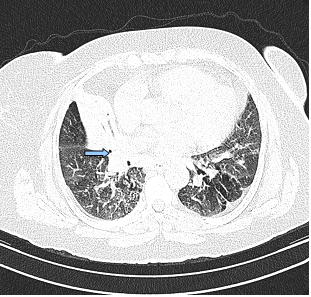

The posterior anterior chest graphy showed consolidation area in right paracardiac region. The high resolution thorax spiral computed tomography (HRCT) obtained on admission revealed consolidation area and atelectasis in right middle lobe (Figure 1). Flexible bronchoscopy (FOB) application was planned to the patient. FOB examination revealed hypervascularisation, hyperemia, deformed bronchial trees and these findings were similar to previous FOB findings. Previous FOB examination has been done to examine middle lobe atelectasis. However, white necrotic lesions were observed in orifice of the middle lobe and at entry of main right bronchus and intermediate bronchus differently from previous bronchoscopic examination (Figure 2, 4). Biopsy from necrotic lesions and bronchus lavage were performed. Histological and cytological findings of material were benign. Microscopic findings of biopsy revealed infection that consists of concentrated lymphoplasmocytes, regular cartilage, and a few polymorph nuclear leucocytes. No AFB was performed on the biopsy specimen. AFB was negative in bronchus lavage; however, mycobacterial cultivation was positive revealing mycobacterium tuberculosis and sensitive to all major tuberculosis agents.

Figure 1

Consolidation area and atelectasis in right middle lobe of the patient